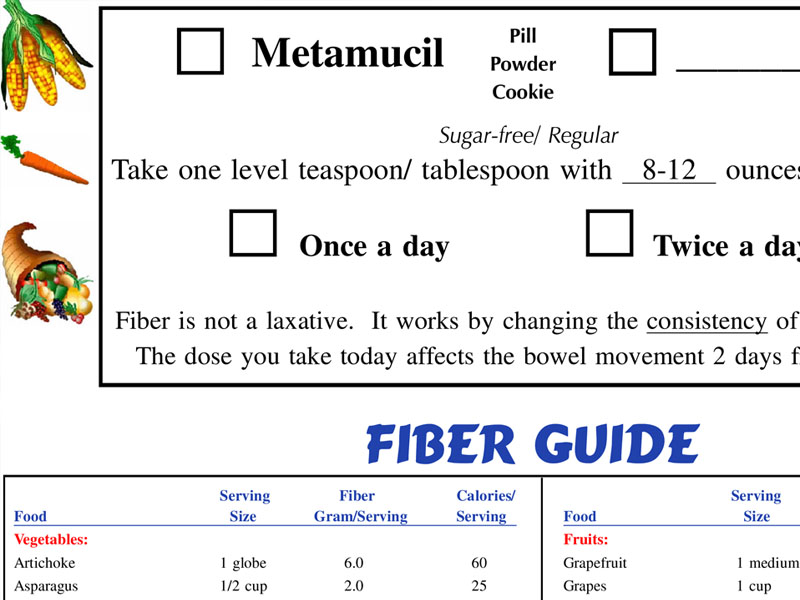

Constipation/Fiber Guide

The ideal bowel movement comes the moment you sit, without pain, straining or bleeding. It's completed within seconds, and is easy to clean.